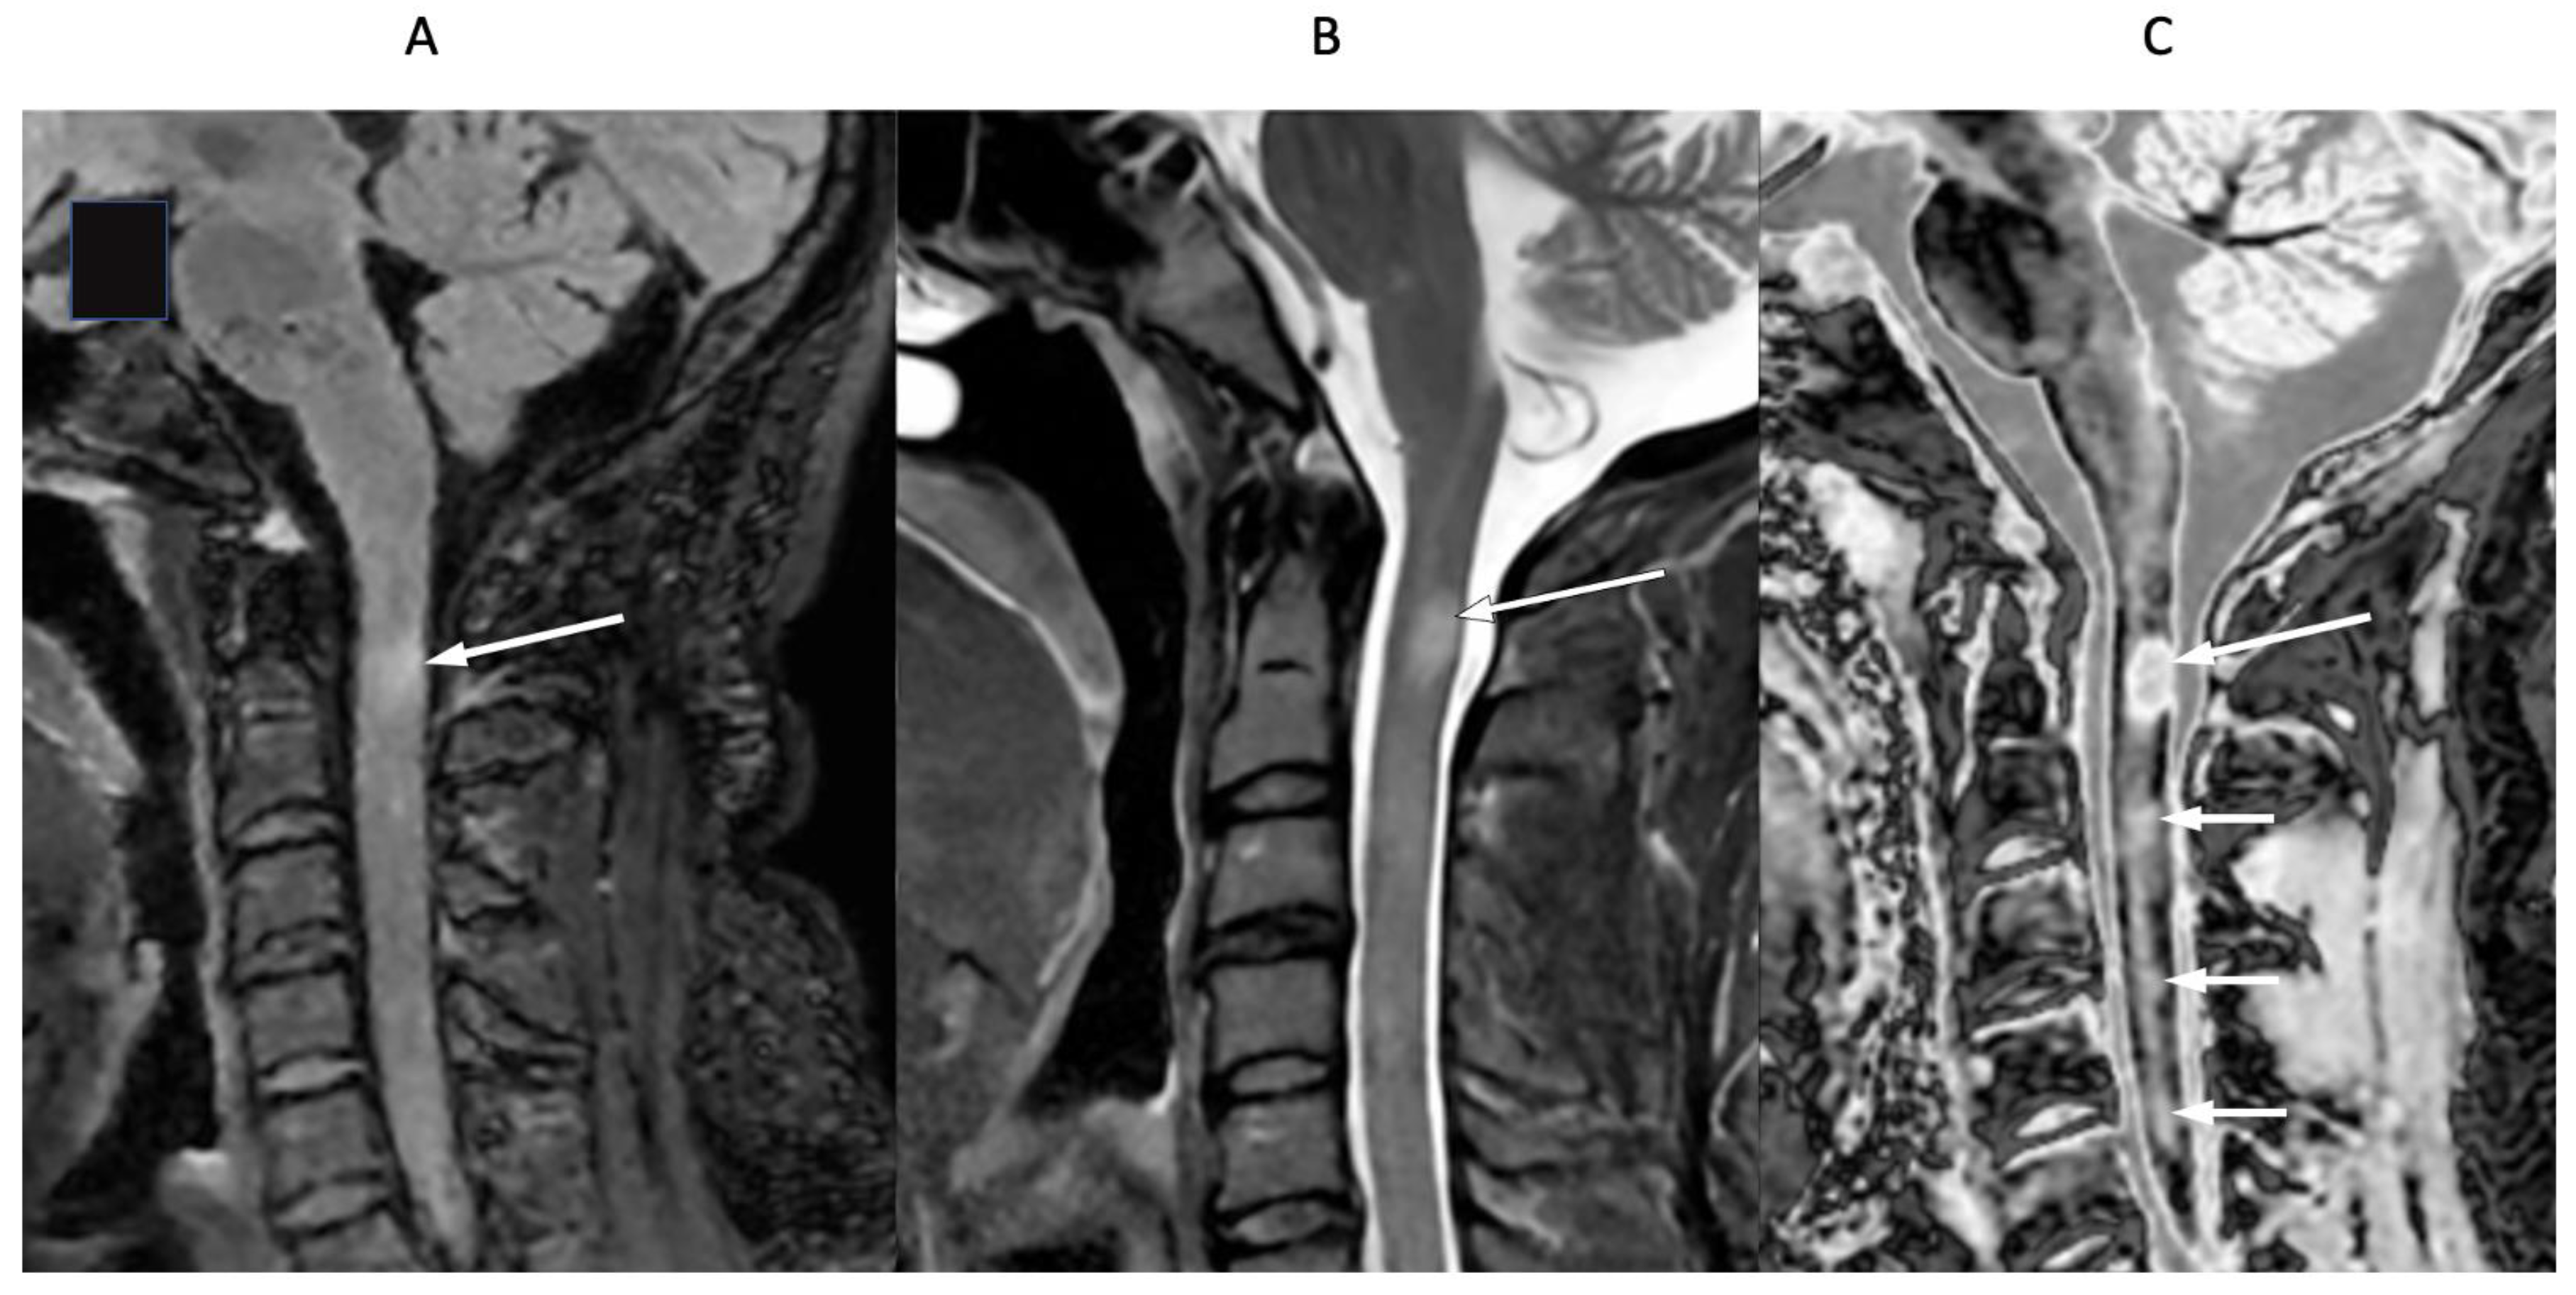

Figure 16 shows the upper cervical spinal cord in a 42-year-old female patient with MS in remission. T2-FLAIR (Figure 16A), T2-wSE (Figure 16B), and wide mD dSIR (Figure 16C) images are compared. A large lesion is seen on all three images, but with greatest contrast on the dSIR image (long white arrows). In addition, three small lesions are only seen on the dSIR image (Figure 16C, short white arrows).

Figure 16.

Forty-two-year-old female patient with MS in remission. Sagittal T2-FLAIR (A), T2-wSE (B), and wide mD dSIR (C) images. A large lesion is seen on all three images but with higher contrast on the dSIR image (long arrows). Three small lesions are only seen on the dSIR image (short arrows).